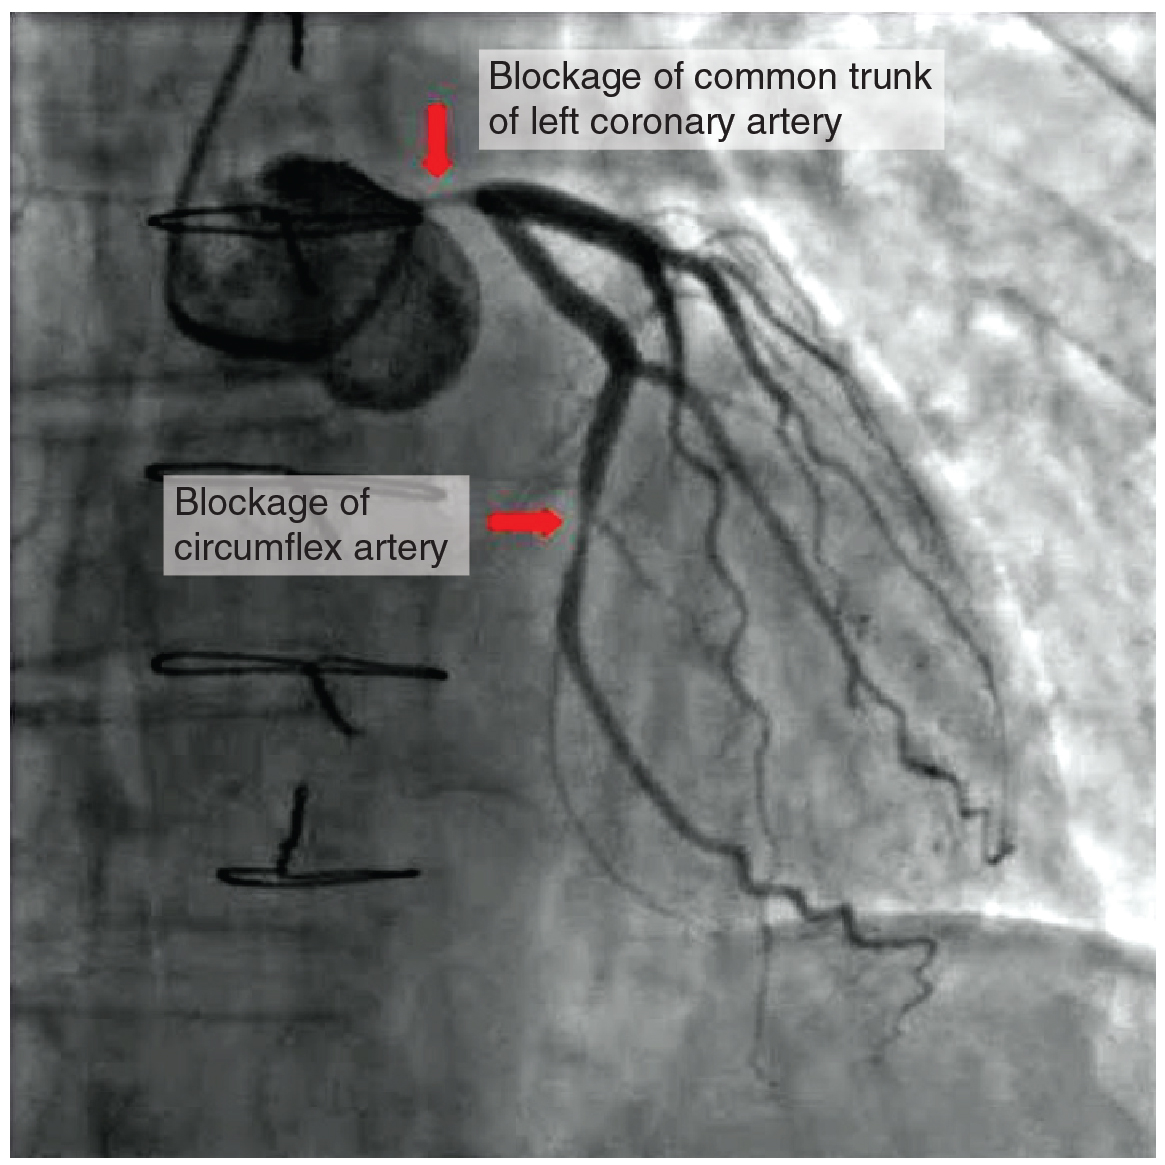

Coronary artery disease is the leading cause of death worldwide. It occurs when the buildup of plaque—a fatty material including cholesterol, connective tissue, white blood cells, and some smooth muscle cells—within the walls of the arteries obstructs the flow of blood and decreases the flexibility or compliance of the vessels. This condition is called atherosclerosis, a hardening of the arteries that involves the accumulation of plaque. As the coronary blood vessels become occluded, the flow of blood to the tissues will be restricted, a condition called ischemia that causes the cells to receive insufficient amounts of oxygen, called hypoxia. (Figure 3.15) shows the blockage of coronary arteries highlighted by the injection of dye. Some individuals with coronary artery disease report pain radiating from the chest called angina pectoris, but others remain asymptomatic. If untreated, coronary artery disease can lead to MI or a heart attack.

The disease progresses slowly and often begins in children and can be seen as fatty “streaks” in the vessels. It then gradually progresses throughout life. Well-documented risk factors include smoking, family history, hypertension, obesity, diabetes, high alcohol consumption, lack of exercise, stress, and hyperlipidemia or high circulating levels of lipids in the blood. Treatments may include medication, changes to diet and exercise, angioplasty with a balloon catheter, insertion of a stent, or coronary bypass procedure.

Angioplasty is a procedure in which the occlusion is mechanically widened with a balloon. A specialized catheter with an expandable tip is inserted into a superficial vessel, normally in the leg, and then directed to the site of the occlusion. At this point, the balloon is inflated to compress the plaque material and to open the vessel to increase blood flow. Then, the balloon is deflated and retracted. A stent consisting of a specialized mesh is typically inserted at the site of occlusion to reinforce the weakened and damaged walls. Stent insertions have been routine in cardiology for more than 40 years.